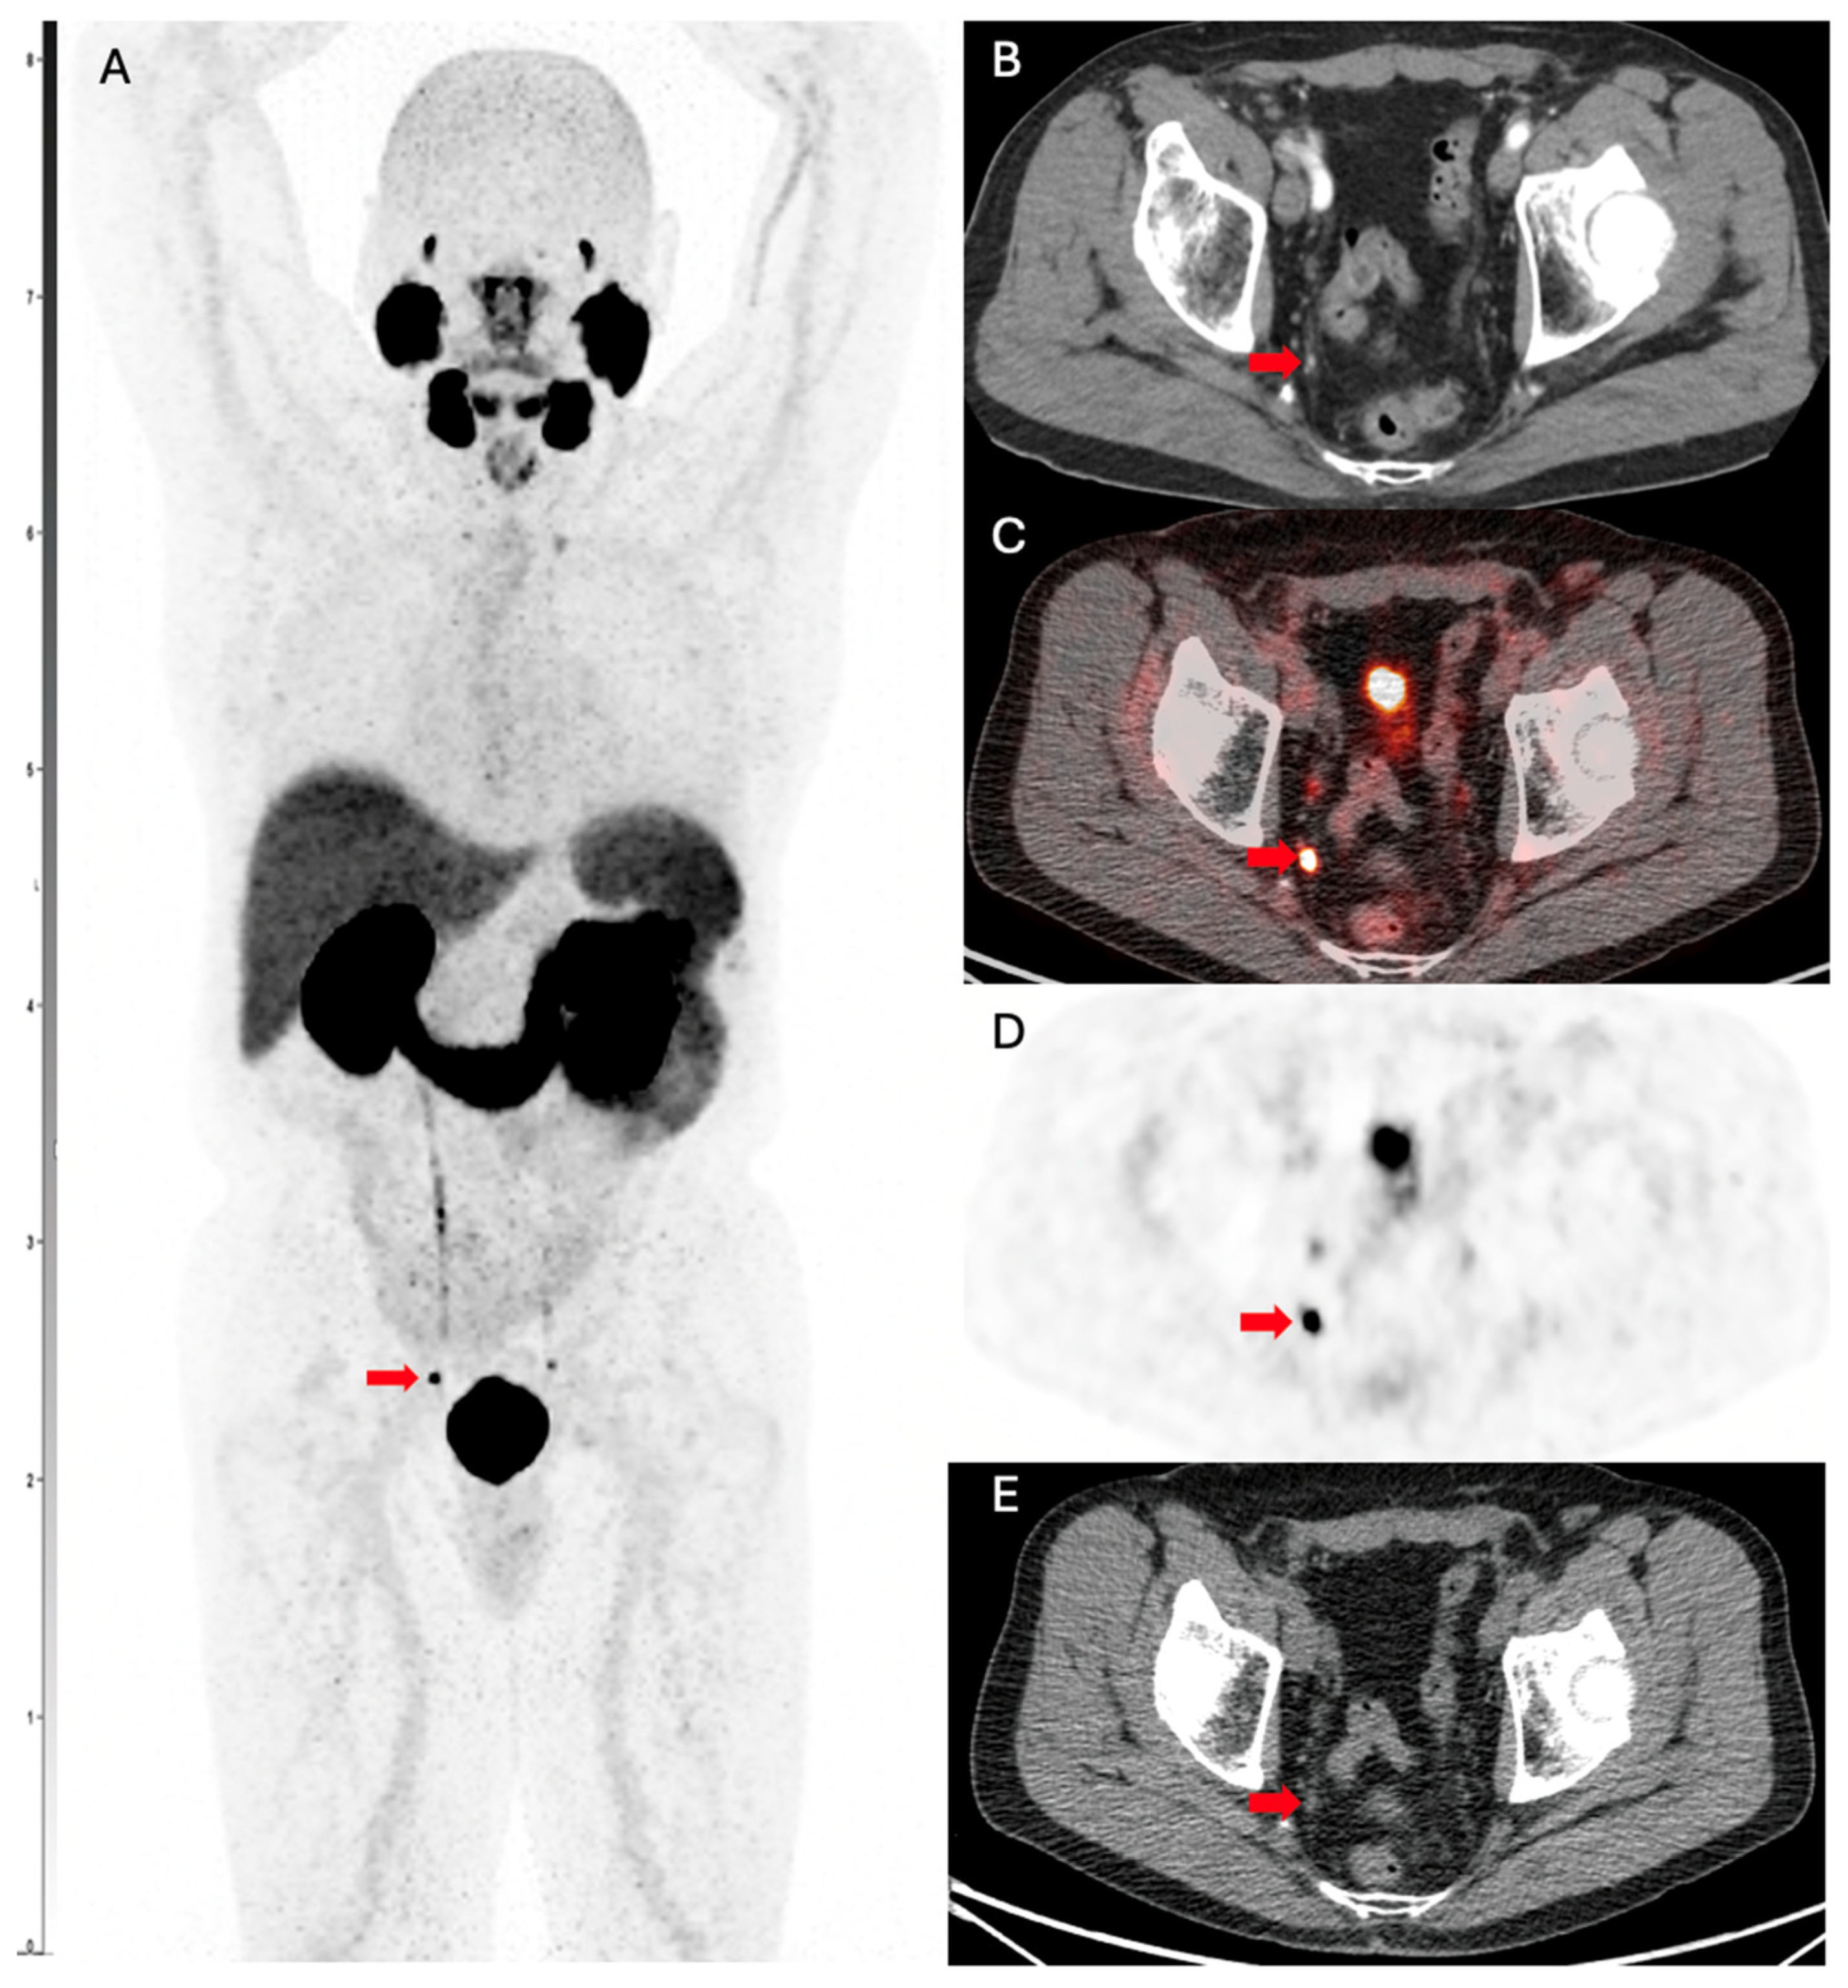

- Qiu, D.-X.; Li, J.; Zhang, J.-W.; Chen, M.-F.; Gao, X.-M.; Tang, Y.-X.; Zhang, Y.; Yi, X.-P.; Yin, H.-l.; Gan, Y.; et al. Dual-tracer PET/CT-targeted, mpMRI-targeted, systematic biopsy, and combined biopsy for the diagnosis of prostate cancer: A pilot study. Eur. J. Nucl. Med. Mol. Imaging 2022, 49, 2821–2832. [Google Scholar] [CrossRef]